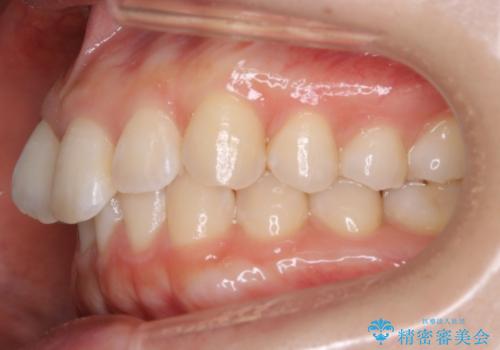

【非抜歯】下の前歯が1本少ない場合の矯正治療

- 前歯のガタつきを主訴に来院されました。

生まれつき下の前歯が1本少なく、その分のスペースを上の前歯がガタつくことで埋めているという状況でした。

上下それぞれのガタつきをとっていく過程で、歯1本分のスペースの差を、上顎の前歯のIPRで調整して並べる方法をご提案させていただきました。